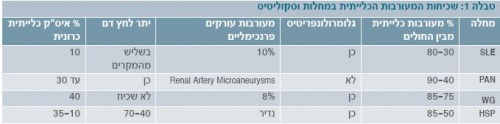

שכיחות המעורבות הכלייתית במחלות השונות

השכיחות של המעורבות הכלייתית במחלות ראומטיות משתנה במחלות השונות (טבלה 1). בחלק מהמחלות משפיעה המעורבות הכלייתית על התחלואה והתמותה של חולים אלו, ולכן חשוב לאבחן חולים הסובלים מפגיעה כלייתית ולטפל בהם. המחלות הראומטיות המפורטות לעיל הן מחלות בהן שכיחה התייצגות כלייתית, כתסמין מרכזי או בליווי תסמינים נוספים.